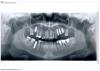

Tasadik Опубликовано 24 октября, 2013 Поделиться Опубликовано 24 октября, 2013 (изменено) Добрый вечер! Очень нужен ваш совет по плану протезирования В декабре 2012г мне установили 5-ть имплантов (их видно на снимке) и через два месяца лечу на второй этап-протезирование. Имплатация проводилась не в России, поэтому очно я встречусь с доком только 15декабря. Можете по снимку дать заочную оценку по приживаемости моих имплантов? Протезировать я планирую все жевательные зубы, т.к. очень хочу поднять на них немного прикус и уже третим этапом протезировать фронтальные зубы. На жевательные планируются коронки из диоксид циркония. А на фронт: низ виниры, а верх пресс керамику.Посмотрите пжл еще три нижних коронки. там металокерамика и десна уже голубая Переделывать боюсь, культи вынимать-попрощаться с зубами 8-й зуб с пломбой завтра иду удалять Он не сложный? Изменено 24 октября, 2013 пользователем Tasadik Ссылка на комментарий

Tasadik Опубликовано 24 октября, 2013 Автор Поделиться Опубликовано 24 октября, 2013 (изменено) Спасибо Все жевательные планируются под коронки.А на фронт верх- на живые виниры, а 4-ре передних пресс керамич коронки. На них же виниры нельзя? В каналах там кутаперча. Меня еще беспокоит как на снимке выглядит 16 имплант, он не сильно глубоко в пазухе? Такое расположение это норма? Сейчас он без нагрузки, а когда будет "одет" не провалится ли в пазуху? Изменено 24 октября, 2013 пользователем Tasadik Ссылка на комментарий

Bier Опубликовано 24 октября, 2013 Поделиться Опубликовано 24 октября, 2013 все нормально, там синуслифтинг сделан. по поводу коронок лучше к ортопедам. Ссылка на комментарий

M@estro Опубликовано 24 октября, 2013 Поделиться Опубликовано 24 октября, 2013 На 4 верхних резца - полные коронки,на клыки - виниры. Коронки слева снизу вызывают определенные вопросы в плане прогноза,особенно на зубе 3.5 Ссылка на комментарий